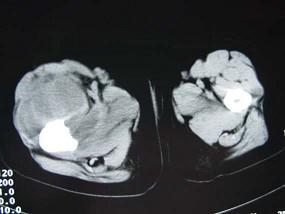

问题 男,15岁,一星期前寒战,继而体温急剧升高,达3940℃,发病后12天患肢右大腿出现功能障碍。局部出现红、肿、热、痛等症状,触之有波动感。实验室检查,血中白细胞升高,血沉增快,血培养阳性,中性粒细胞轻度升高,请结合所提供的图像,选择最佳选项 ( )

选项 A、动脉瘤样骨囊肿 B、骨巨细胞瘤 C、慢性化脓性骨髓炎 D、软骨肉瘤 E、急性化脓性骨髓炎

答案 E